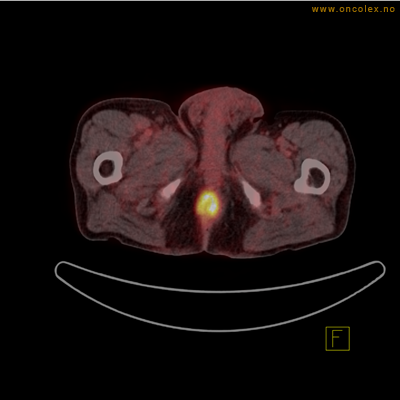

Vev som tar opp mer radioaktivt stoff, synes som hvite områder som lyser opp mer i forhold til annet vev som tar opp mindre sukker.

Høyt opptak av 18F-FDG i adenokarsinom i rektosigmoideumovergangen. Fysiologisk opptak i blæren.